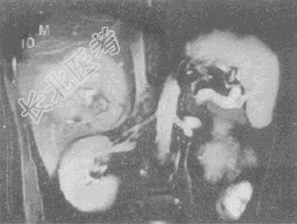

- 单项选择题男,36岁, 腹胀、消化不良、消瘦、中上腹痛,影像检查如下图, 最可能的诊断是

A、胃间质肉瘤并肝转移

B、胃间质瘤并原发性肝癌

C、内胚窦瘤肝转移

D、胃淋巴瘤伴原发性肝癌

E、胃间质瘤并肝血管瘤